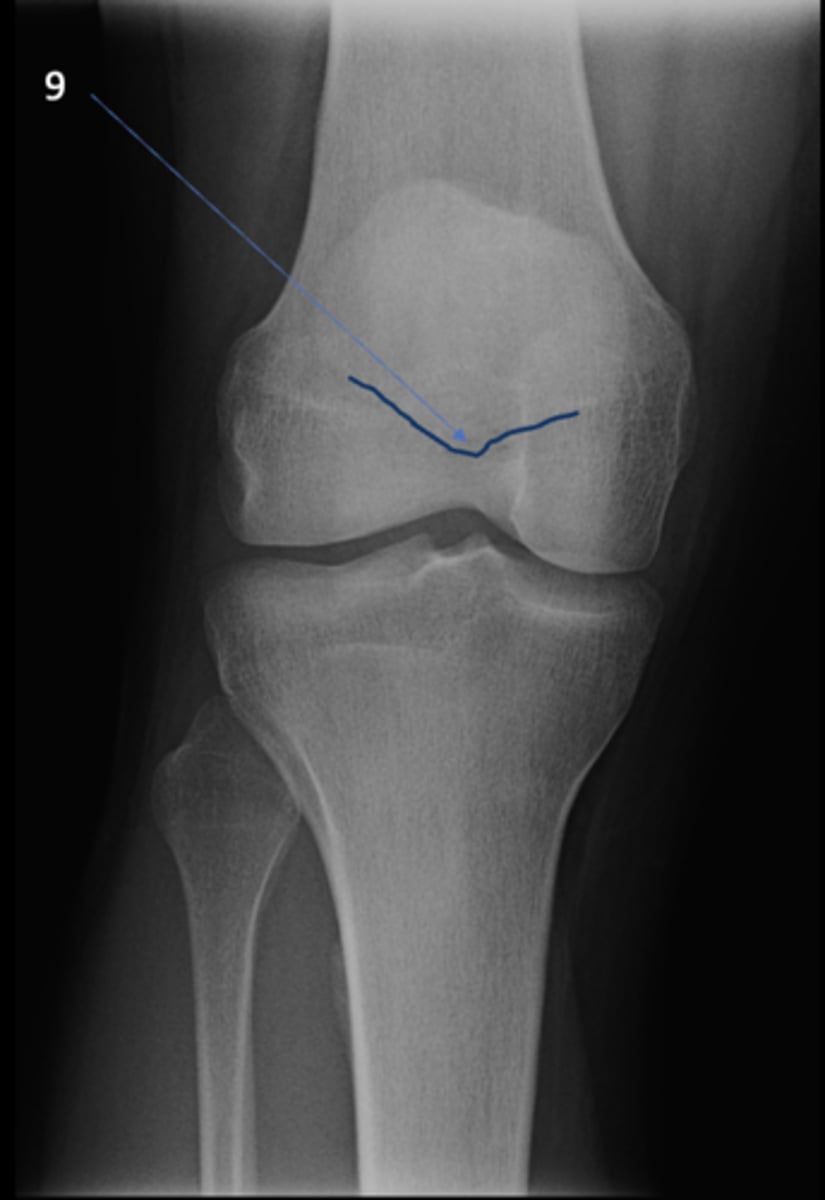

AP knee

View?

Fibular head

ID 1

Apex of fibular head

ID 2

Fossa for popliteal tendon

ID 3

Intercondylar eminence

ID 4

Superior aspect of patella

ID 5

Lateral femoral condyle

ID 6

Medial femoral condyle

ID 7

Intercondylar fossa

ID 8

Apex of patella

ID 9

Lateral femoral epicondyle

ID 10

Medial femoral epicondyle

ID 11

Tibial tuberosity

ID 12

Medial tibial plateau

ID 13

Lateral tibial plateau

ID 14

Medial tibial condyle

ID 15

Lateral tibial condyle

ID 16

Physeal scar

ID 17

Adductor tubercle

ID 18